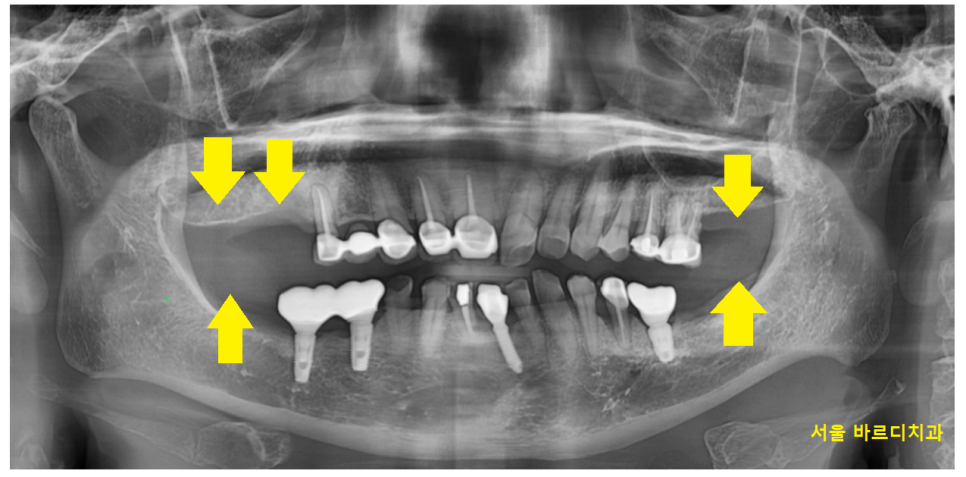

골다공증 약물 복용 중

골 흡수를 하는 성분을 지닌 약을 드시는데

임플란트를 하게 되면

치유가 지연되게됩니다.

간혹 최악의 경우 뼈가 썩기도하고요ㅠㅠ

이런것 때문에 골다공증 치료중 임플란트

어렵다고 말씀드리는데요.

다행히 중단 후 치과 치료가 가능하신 상태였습니다.

충분히 휴지기를 가지고

암사동 임플란트 진행하기로 하였습니다.